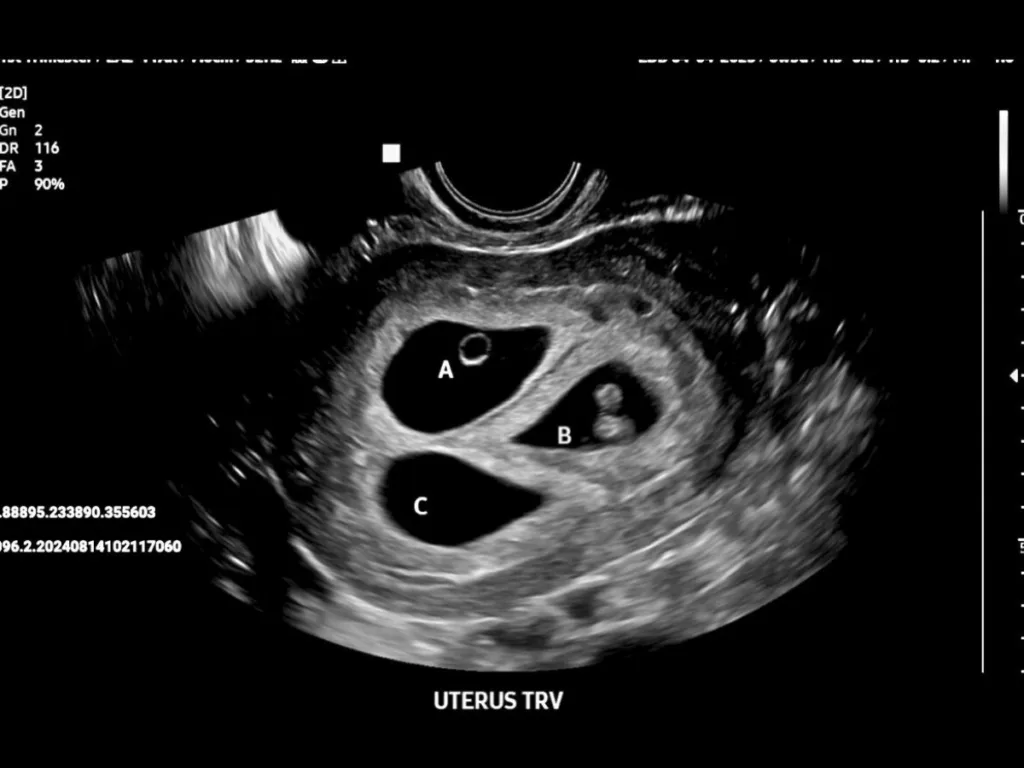

“Surprise… it’s triplets!” the sonographer beamed.

The 6-week scan shattered every expectation. No twins. Triplets. Our jaws hit the floor. Daniel’s eyes widened in pure awe: “Three babies… in there?”